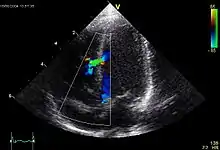

.jpg.webp) Echokardiogramm eines ASD II, d.h. Ostium-secundum-Typ. |

Atrial septal defect (ASD)

ASD II:

Das heruntergewachsene Septum primum reisst normalerweise in der Mitte ein und bildet das Foramen secundum bzw. Foramen ovale. Dieses wird durch das links vom Septum primum ebenfalls von oben herunterwachsende Septum secundum gardinenartig bedeckt (Ventil) und kurz nach der Geburt durch Umkehr der Druckverhältnisse funktionell (z.T. strukturell durch Verklebung) verschlossen. Ist der Verschluss so ungenügend, dass es zum Links-rechts-Shunt kommt, spricht man vom offenen Foramen ovale bzw. ASD II. Der ASD II ist im Ggs. zum ASD I weiter oben lokalisiert. Er macht oft wenig Symptome und wird oft erst im Erwachsenenalter erkannt. Der Links-Rechts-Shunt kann im EKG zu Zeichen der Rechtsherzbelastung führen (Rechtslagetyp, P pulmonale, inkompletter Rechtsschenkelblock ohne Hypertrophie-Zeichen (rsr's') als Zeichen der rechtsventrikulären Volumenbelastung) und bei starker Ausprägung zu klinischen Symptomen führen.

Echokardiogramm eines VSD. |